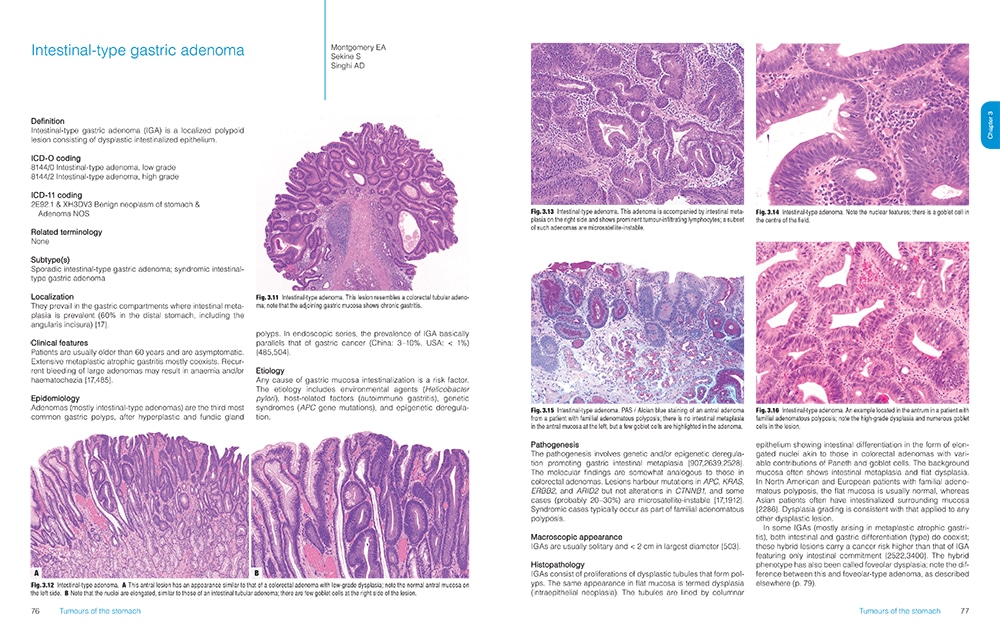

Featuring more than 1,000 high-resolution color graphics, Digestive System Tumours, the first volume of the fifth edition of the WHO series known as the Blue Books, brings a noticeable improvement in image quality and graphic design over the fourth edition, published in 2008. The book’s two-column layout, replacing the former three-column design, allows for enlarged images throughout. And this book is the first to be produced in both a print version and an online subscription version that includes whole-slide imaging.

The fourth edition of the WHO series set a whole new standard and raised the bar considerably from the third edition, Dr. Cree says. “And we are honestly trying to do the same with the fifth edition.” The new online subscription feature, for example, is intended not only to make user access easier but also to show significantly more content. “We have a whole-slide image for each diagnosis in the book. Whole-slide images allow us to get an overview of the entire section of the slide right down to the individual cells and see what is going on.” In addition, each paper in the book has a direct online link to the evidence that underpins the paper, he notes.

Pathologists learn so much from their exposure to illustrations, he says, and high-quality graphics have always been a feature of the WHO Blue Books. “When you collect world experts together and they all have their archives of gross photographs and microscopic slides, you can produce the best examples and most classic illustrations of the features.”

Now, the incorporation of digital slides will allow an interactive experience for the reader, who will be able to look at not just a single snapshot, such as would appear in a book, but also different magnifications that can be examined more comprehensively. This capability has become practical only in the past few years, Dr. Klimstra says. The WHO has learned from the experience of PathPresenter, which has created an educational portal for digital slides that is now an entirely new feature of the WHO series.